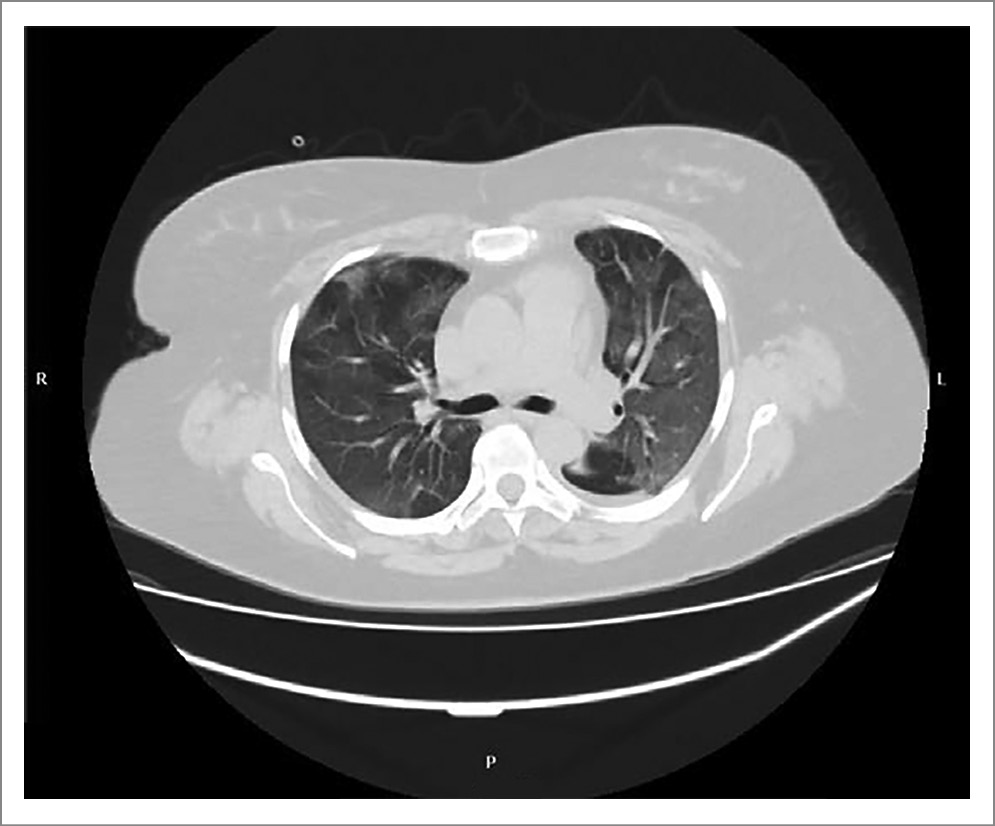

На 6-й день заболевания появились выраженные признаки дыхательной недостаточности: снижение сатурации крови (метод пульсоксиметрии) до 84% при дыхании атмосферным воздухом, при инсуффляции увлажненного кислорода 12 л/мин – до 94–95%. Выполнена повторная МСКТ органов грудной клетки, отмечалось увеличение размеров очагов уплотнения типа «матового стекла», появление новых аналогичных очагов. КТ-признаки вирусной инфекции, с высокой вероятностью COVID-19, среднетяжелой (КТ-3) степени тяжести (рис. 2).

Рис. 2. Пациентка П. МСКТ органов грудной клетки (6-й день госпитализации).